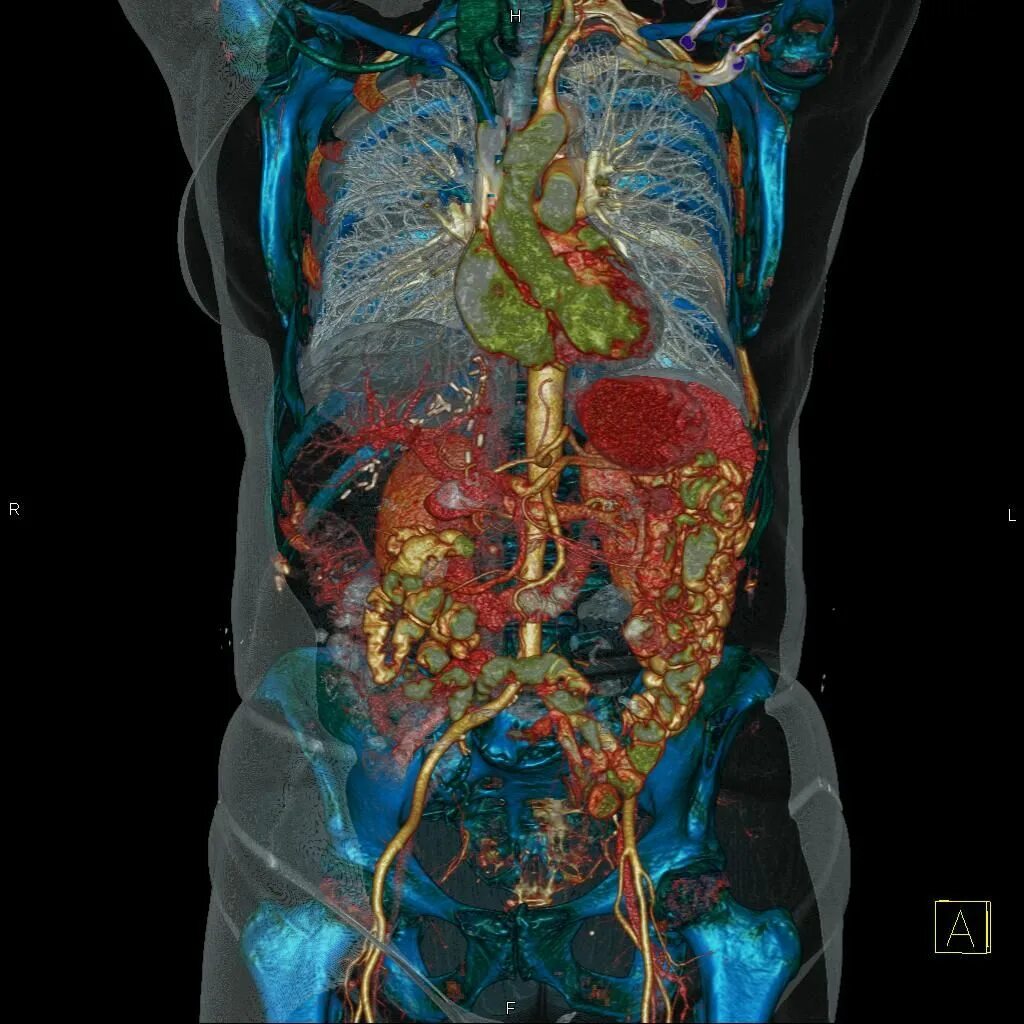

3 обп